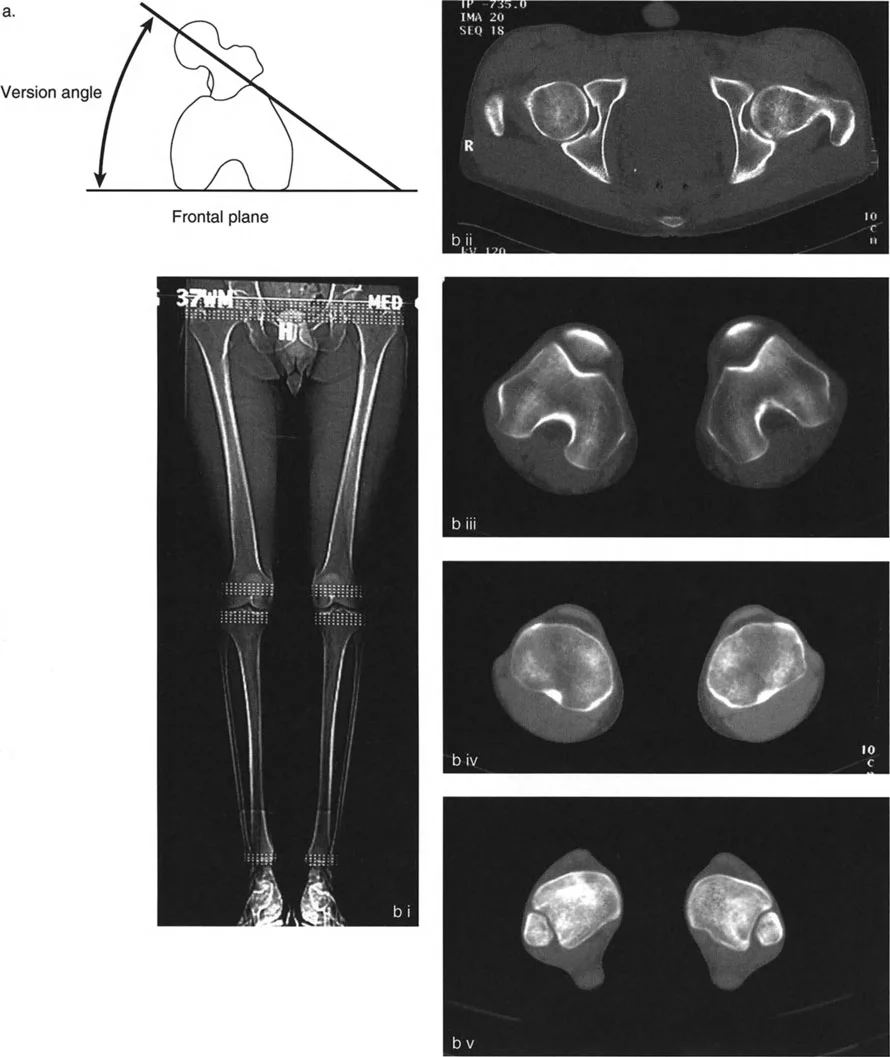

2. التصوير بالأشعة السينية (X-rays)

تعتبر الأشعة السينية هي الأداة التشخيصية الأساسية لتشوه الانزياح. يتم التقاط صور متعددة من زوايا مختلفة (عادةً الأمامية-الخلفية AP والجانبية LAT، وقد تشمل صوراً مائلة Oblique) للحصول على رؤية شاملة للتشوه.

- تحديد مستوى الانزياح: تظهر الأشعة السينية بوضوح المنطقة التي حدث فيها الانزياح.

- قياس حجم الانزياح (Magnitude): يتم قياس المسافة التي تحركها أطراف العظم بالمليمترات.

- تحديد اتجاه الانزياح (Direction): يتم وصف اتجاه الجزء البعيد من العظم بالنسبة للجزء القريب (مثلاً: أمامي، خلفي، إنسي، وحشي، أو مزيج منها).

- تحديد مستوى الانزياح (Level): يتم تحديد المنطقة التي تتداخل فيها أطراف العظم، والتي غالباً ما تكون مرتبطة بالتقصير.

- تقييم التلامس العظمي: تساعد الأشعة السينية في تحديد مدى فقدان التلامس بين أطراف العظم، وهو مؤشر مهم لعدم التئام الكسور.

- الأشعة المائلة (Oblique Radiographs): في بعض الحالات، قد لا يظهر الانزياح بوضوح في الصور الأمامية-الخلفية أو الجانبية، مما يستدعي صوراً مائلة للكشف عن التشوه الحقيقي، خاصة في حالات الانزياح في المستويات المائلة.

4. التصوير المقطعي المحوسب (CT Scan)

في حالات أكثر تعقيداً، خاصة عندما يكون هناك شك في وجود تشوهات ثلاثية الأبعاد أو لتخطيط جراحي دقيق، قد يطلب الدكتور هطيف إجراء تصوير مقطعي محوسب. يوفر التصوير المقطعي صوراً تفصيلية للعظم والأنسجة المحيطة به، مما يساعد في:

* رؤية ثلاثية الأبعاد للتشوه: يسمح بتقييم دقيق للتشوه من جميع الزوايا.

* تحديد مدى عدم الالتئام: يظهر بوضوح ما إذا كان هناك نسيج ليفي يمنع التئام العظم.

5. قياس محور الحمل الميكانيكي (Mechanical Axis Deviation - MAD)

يُعد قياس محور الحمل الميكانيكي أمراً حاسماً، خاصة في تشوهات عظم الفخذ والساق التي تؤثر على مفصل الركبة. يتم ذلك باستخدام صور الأشعة السينية الطويلة التي تشمل الورك والركبة والكاحل. يساعد هذا القياس في:

* تقييم تأثير الانزياح على المفصل: تحديد مدى تأثير الانزياح على توزيع الضغط في الركبة.

* تخطيط التصحيح الجراحي: توجيه الجراح لتصحيح الانزياح بطريقة تعيد المحاذاة الميكانيكية الطبيعية.